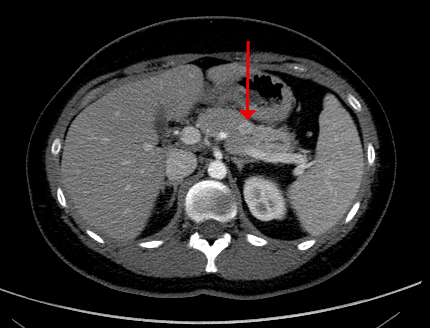

Radiology description

- PanNETs are usually well circumscribed, solid and avidly enhancing lesions (Radiol Clin North Am 2016;54:441)

- Sensitivity of imaging technique for PanNETs: endoscopic ultrasound (EUS) ~90%, computed tomography (CT) 63 - 82%, magnetic resonance imaging (MRI) 85 - 100% (AJR Am J Roentgenol 2021;217:245, Ann Gastroenterol 2015;28:193)